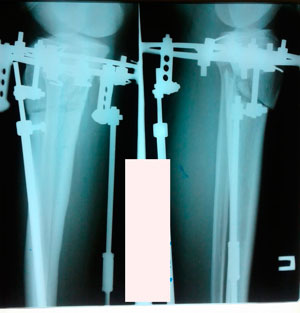

Дата операции - 19.11.2019г.

Дата снятия аппаратов - 18.02.2020

Срок сращения - 89 дней.

image-25-02-20-01-43-9.jpg

image-25-02-20-01-43-8.jpg